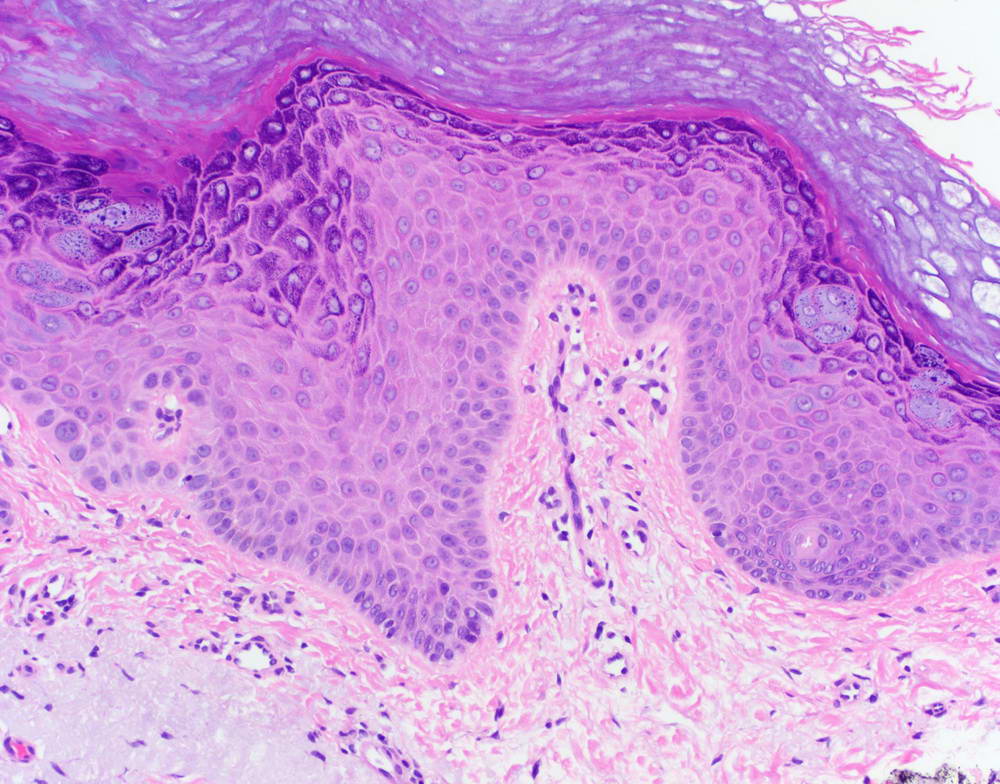

Η ακτινική υπερκεράτωση (< ακτίνα ηλίου) ή αλλιώς ηλιακή υπερκεράτωση αναφέρεται σε μια δερματική βλάβη που παρουσιάζεται με τραχείς, ξηρές και φολιδωτές αυξήσεις και προκαλείται κυρίως από την χρόνια έκθεση στην υπεριώδη ηλιακή ακτινοβολία (UV).

Αρχικά, αναπτύσσεται ως πολλαπλές (1-2 mm) κηλίδες στο δέρμα, ευκολότερα αισθητές παρά ορατές, που με την πάροδο του χρόνου μεγεθύνονται ελαφρώς και συνήθως γίνονται ανάγλυφες, κοκκινωπές ή καφεοειδείς και φολιδωτές. Σε κάποιες περιπτώσεις, μπορεί να έχουν και κωνοειδή μορφή πάνω από την επιφάνεια του δέρματος (δερματικό κέρας).

Η ακτινική υπερκεράτωση συνιστά τύπο προ-καρκινικής βλάβης και ο κίνδυνος μεταγενέστερης μετάλλαξής της σε καρκίνο (ακανθοκυτταρικό καρκίνωμα, τη δεύτερη πιο κοινή μορφή) αν αφεθεί χωρίς θεραπεία, μέσα σε διάστημα 10 ετών ανέρχεται σε 6% - 10%.

Η διάγνωση γίνεται με φυσική εξέταση. Αν ο ιατρός κρίνει ότι χρειάζεται περαιτέρω διερεύνηση, μπορεί να συστήσει και βιοψία, ώστε δείγμα από την δερματική βλάβη να σταλεί για ανάλυση στο εργαστήριο, ελέγχοντας την υποψία τυχόν πρώιμου καρκίνου.